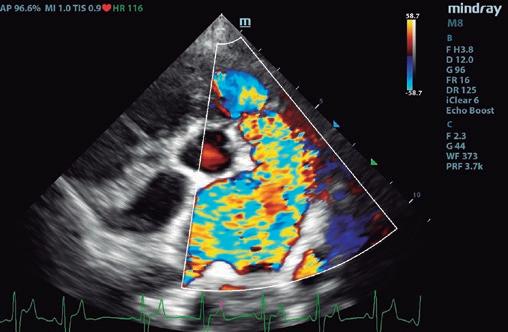

Boehringer Ingelheim España ha programado hasta final de año las Jornadas de Ecografía Avanzada patrocinadas por Vetmedin que recorrerán diversas ciudades del territorio nacional junto al referente Germán Santamarina. La finalidad de la iniciativa es brindar formación especializada y participativa a los especialistas en ecografía ambulante, un colectivo con necesidades muy específicas al cual Boehringer Ingelheim brinda su apoyo.

Las jornadas comenzaron en Barcelona y Alicante los días 21 y 22 de junio, respectivamente. Madrid, País Vasco y Andalucía y Canarias serán las siguientes durante las semanas del 23 de octubre y del 13 de noviembre. Todas las sesiones tienen una duración de medio día y se desarrollan en formato de mesa redonda a partir de las 15:00 h.

Con el objetivo de promover una experiencia más cercana e interactiva, las sesiones se organizan en grupos pequeños, con un límite de 10 a 15 participantes por sesión.